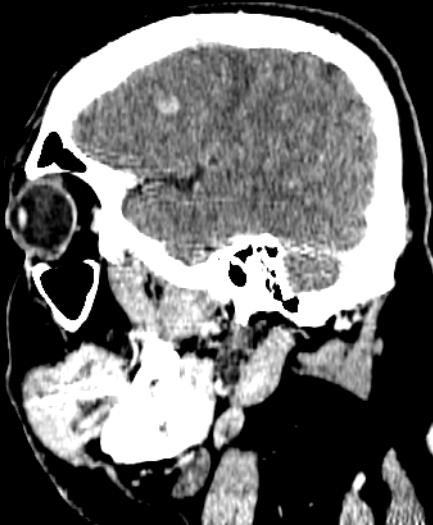

La angiotomografía cerebral evidencia la presencia de múltiples áreas hiperdensas de distribución difusa, bilateral que compromete ambos lóbulos frontales, compatibles con hemorragias intraparenquimatosas de focos múltiples, asociado a edema perilesional (Fig 1 y 2), además se identificó la presencia de signo del delta vacío secundario a trombosis venosa dural que compromete el seno sagital superior, con extensión a la confluencia de los senos, seno transverso derecho, así como el seno yugular y vena yugular ipsilateral (Fig 3 y 4).

Figura 1,2: Imágenes de angiotomografía cerebral en proyección axial y sagital, en ventana de cerebro que muestra la presencia de múltiples áreas hiperdensas en lóbulos frontales, de distribución difusa, bilateral.